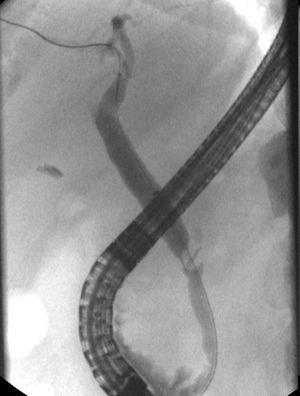

69-year old female presented with a monthlong abdominal pain and nausea with vomiting. Initial workup showed mild increase of aminotransferases (AST, 64.8U/L; ALT, 99.6U/L). Ultrasound was unremarkable. Few days later aminotransferases increased (AST, 1652U/L; ALT, 1785U/L), with elevated total bilirubin (1.7mg/dL), CRP (47mg/L) and leukocytosis. Her medical history was notable for laparoscopic cholecystectomy 17 years earlier during which cystic duct and artery were ligated. During current work up patient underwent endoscopic ultrasound that showed 11mm gallstone in the bile duct. At subsequent ERCP a 10mm×6mm suspected stone with a central oval radiopaque defect (Fig. 1) in the common hepatic duct at the level of cystic duct was successfully extracted. Surgical clip within the stone was identified (Fig. 2).

Surgical clip migration is an uncommon complication of laparoscopic cholecystectomy, which may occur days to years following surgery and can lead to clip-related biliary stones.1 The exact mechanism is not fully understood. Some authors hypothesize that clip migration is consequence of the pressure induced by surrounding structures such as liver on the clipped cystic duct, which is inverted into the lumen of the common bile duct.2 Clip migration with gallstone formation should be considered in the differential diagnosis of postcholecystectomy biliary colic and cholangitis. Management with ERCP is the treatment of choice although some cases require surgical therapy.